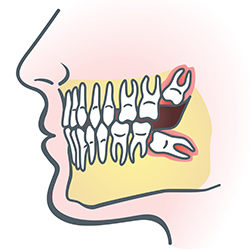

Wisdom teeth

Services provided by General Dentists.

Wisdom teeth are molars found in the very back of your mouth. They usually appear in late teens or early twenties, but they may become impacted (fail to erupt) due to lack of room in the jaw or angle of entry. When a wisdom tooth is impacted, it may need to be removed. If it is not removed, you may develop gum tenderness, swelling, or even severe pain. Impacted wisdom teeth that are partially or fully erupted tend to be quite difficult to clean and are susceptible to tooth decay, recurring infections, and even gum disease.

Wisdom teeth are typically removed in the late teens or early twenties because there is a greater chance the roots have not fully formed and the bone surrounding the teeth is less dense. These two factors can make extraction easier as well as shorten the recovery time.

In order to remove a wisdom tooth, your dentist first needs to numb the area around it with a local anesthetic. Since the impacted tooth may still be under the gums and embedded in your jawbone, your dentist will need to remove a portion of the covering bone to extract the tooth. In order to minimize the amount of bone that is removed with the tooth, your dentist will often "section" your wisdom tooth so that each piece can be removed through a small opening in the bone.

Once your wisdom teeth have been extracted, the healing process begins. Depending on the degree of difficulty related to the extraction, healing time varies. Your dentist will share with you what to expect and provide instructions for a comfortable, efficient healing process.